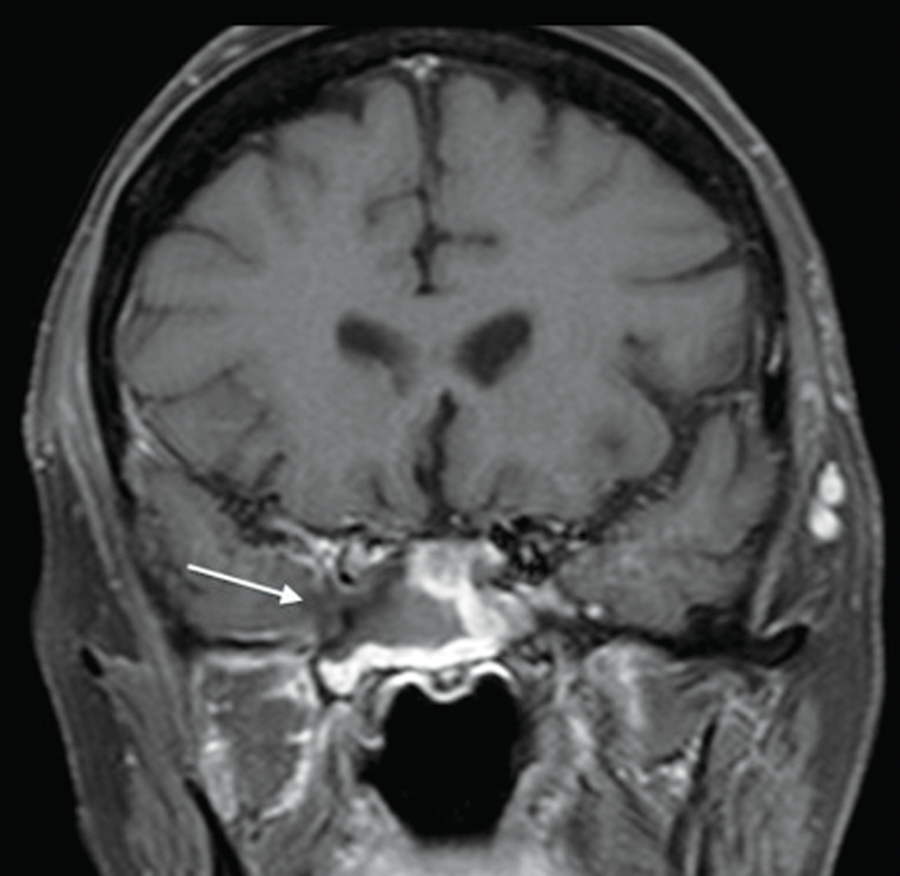

Magnetic resonance imaging (MRI) is an imaging modality utilised infrequently in the assessment of chronic rhinosinusitis. However, its role becomes essential where there is concern for intracranial complications secondary to acute or chronic sinus inflammatory disease or where there is concern for the presence of sinonasal neoplasia. Chronic rhinosinusitis is a common presentation in the immunocompetent population. However, certain immunocompromised patient groups are at significant risk of aggressive infective aetiologies centred in and around the paranasal sinuses which can extend intracranially. A high index of suspicion for aggressive invasive fungal sinusitis is recommended in patients with acute myeloid leukaemia or poorly controlled insulin-dependent diabetes mellitus for example and, as such, the threshold for MRI assessment of such patients should be low. High-morbidity and high-mortality complications such as cavernous sinus thrombosis, internal carotid artery occlusion or pseudoaneurysm formation, brain parencymal infarction and haemorrhage can develop secondary to the invasive fungal infection. The fungal infection can also directly affect the bony architecture of the sinonasal region with resultant bone necrosis. It is therefore imperative that the infection is recognised early and treatment initiated (Figure 2).

Figure 2: Contrast-enhanced fat-saturated T1 weighted coronal MR image in a patient with acute myeloid leukaemia, deteriorating right cranial nerve function and headache confirms chronic invasive fungal sphenoid sinusitis: low signal invasive fungal inflammatory tissue centred on the right sphenoid sinus and invading the right lateral wall of the sphenoid sinus, right cavernous sinus and encasing the cavenous segment of the right internal carotid artery (arrow).